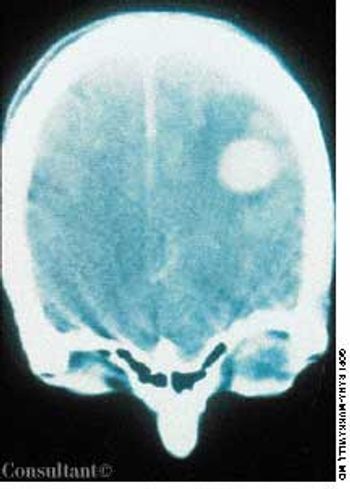

After suffering with recurrent, diffuse, daily headaches for 4 months, a 51-year-old woman sought medical advice. She described the headaches as severe and said they were affected by the position of her head, particularly when bending forward. She also reported episodes of transient numbness on her right side. No syncope was noted, and the patient denied nausea and vomiting.